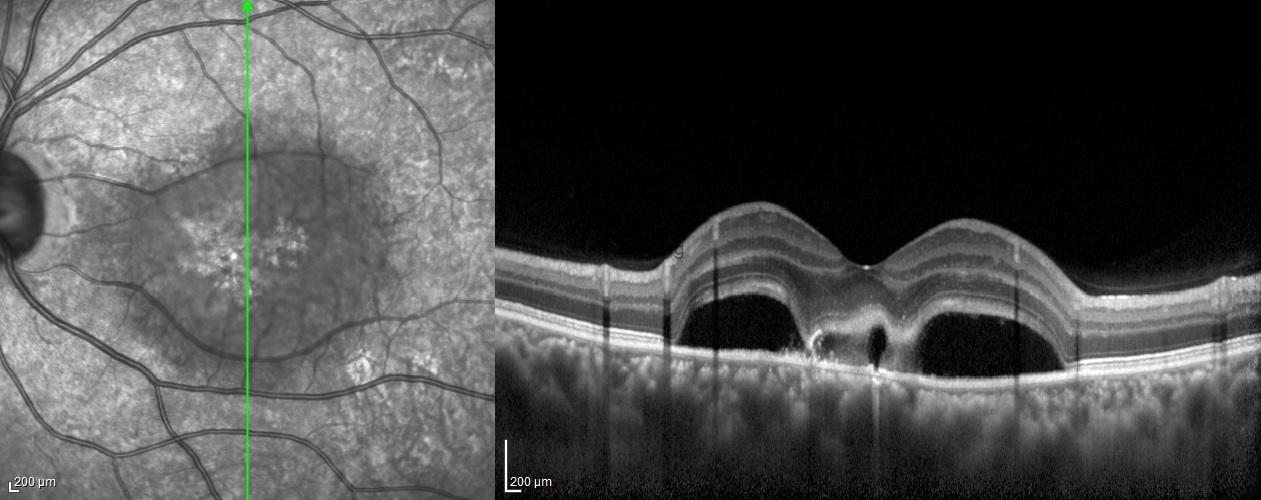

Dilated fundus examination demonstrated while the posterior segment of the right eye was completely normal, in the left eye there was a well-defined diffuse serous retinal detachment, a yellowish subretinal fibrinous material accumulation adjacent to the fovea, and a darker spot within the yellowish fibrin.

The spectral domain OCT scan passing through the area of fibrinous material revealed serous detachment, hyper-reflective fibrinous material accumulation extending from the RPE to the subretinal area within the detachment area, and two vacuolar structures visible as hyporeflective spaces amid the hyper-reflective fibrin.

Optic coherence tomography has an important role in the diagnosis and follow-up of central serous chorioretinopathy. Several OCT studies have demonstrated hyper-reflectivity in the subretinal space corresponding to the fibrin material and have also demonstrated dipping of the neurosensory retina at the site of fibrin formation. Sometimes, this fibrin accumulation has hyporeflective areas and has been named the vacuole sign. It was reported that the presence of a hyporeflective vacuole amid the hyper-reflective fibrin adjacent to RPE defects probably indicates the site of constant fluid egress. It was also emphasized that the vacuol sign could be an important indicator of disease activity, especially in cases where angiography is not possible.